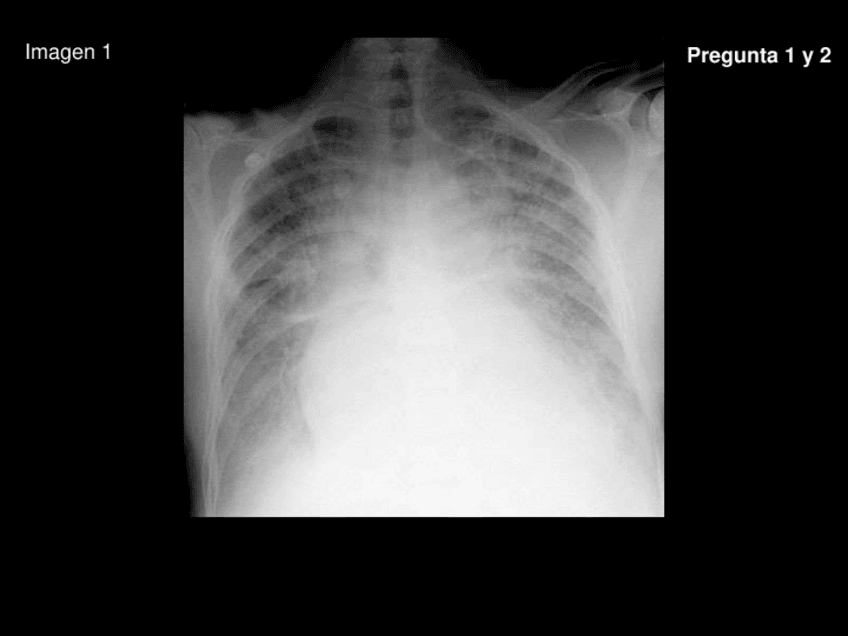

Exámenes - examen-practico-2.pdf

24 páginas